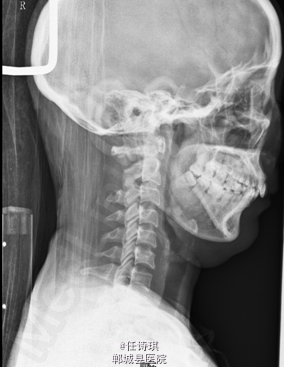

女,46岁8月,因“颈部不适3年,右上肢软弱疼痛伴双下肢胀痛1年”入院。3年前无明显诱因出现颈部不适,以局部胀痛为主,劳累后加重休息后可缓解,不伴上肢放射痛。遂未予特殊处理。1年前出现右上肢酸麻肿痛,以肘关节疼痛和手部皮肤麻木为主,行走约10分钟后自觉双小腿后侧胀痛,休息后可缓解。在当地医院诊断为“网球肘、颈椎病”予以对症治疗,但上述症状无明显改善。行MRI、CT等检查,诊断为“C2椎管内肿瘤”,未予特殊治疗。为求进一步诊断今日由门诊以“C2椎管内占位,性质?”收入院

专科查体:视:脊柱无明显畸形。触:颈胸部各棘突无明显压、叩痛。四肢肌张力正常,右手皮肤触觉减退。动量:右侧上肢肌力IV级,左侧肢体V级。右侧上肢腱反射活跃,双侧膝腱反射活跃,跟腱反射正常引出。Hoffman征阳性,Babinski征未引出。外院MRI示:C2椎管内脊髓背侧占位病变,脊膜瘤可能。T2椎体内异常信号,多为血管瘤。。

初步诊断:1、颈2节段椎管内占位伴不全四肢瘫(Frankel D):脊膜瘤?黄韧带骨化? 2、胸2椎血管瘤 处理:全麻下行经后路颈2全椎板切除、椎管探查减压、椎管内占位切除活检术,